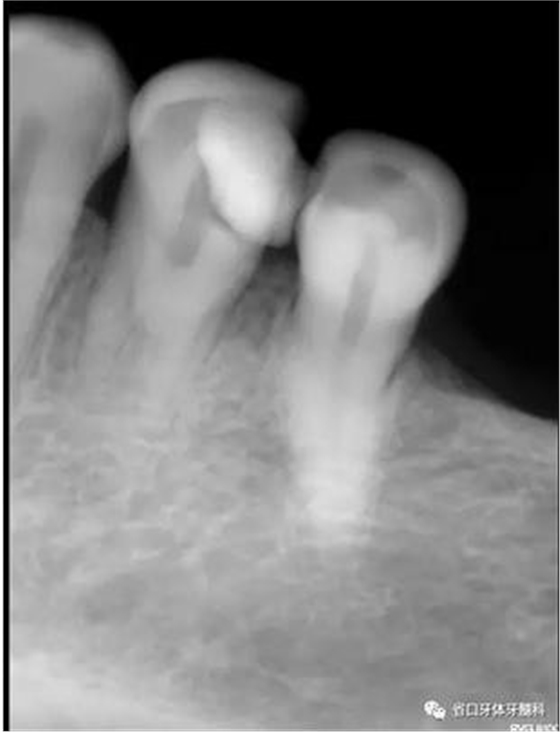

圖1:術(shù)前X線片:34遠(yuǎn)中高密度影及髓,疑似雙根管

圖2:術(shù)前CBCT:在根管中下段分叉為雙根管,頰側(cè)為”C”型根管

1、以單根管為主的下頜第一前磨牙,由于發(fā)育上的特點(diǎn),根管系統(tǒng)存在較大變異,可能是最難以進(jìn)行根管清潔和成型的一組牙齒,常因?yàn)楹雎粤穗p根管及多根管的存在,造成遺漏根管發(fā)生。本病例中,34的術(shù)前X線片可見,主根管影像突然消失,提示我們可能存在多根管,CBCT的有助于我們了解根管分叉位置和根管的彎曲情況,全程顯微鏡下治療有助于我們進(jìn)行髓底探查及進(jìn)行有效預(yù)備根充。